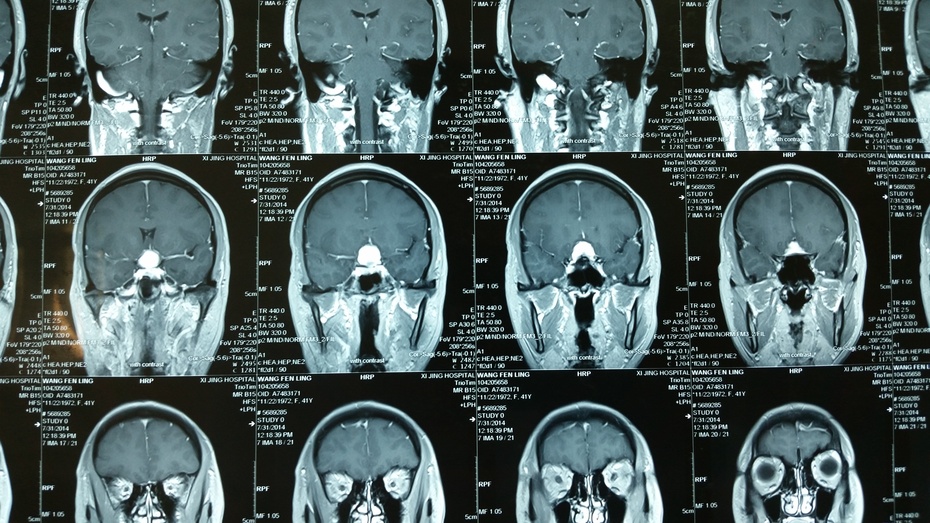

湘南学院附属医师-神经外科:鞍结节区脑膜瘤(1月24号手术))

鞍结节脑膜瘤诊断治疗